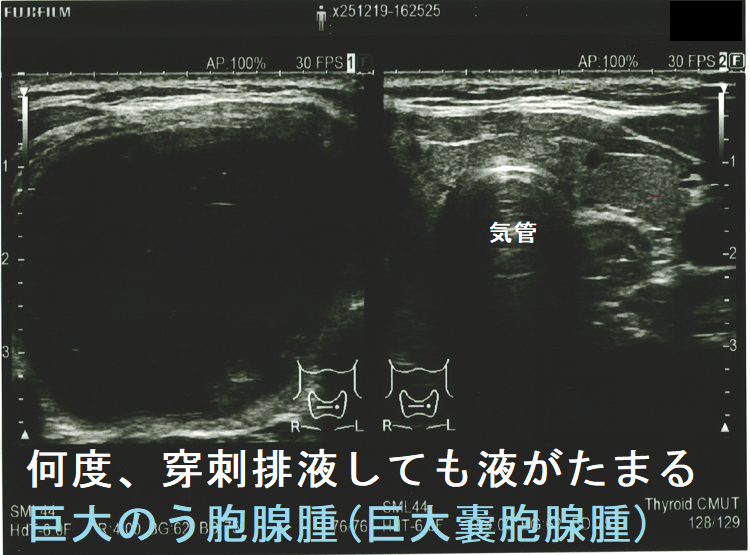

巨大のう胞腺腫(巨大嚢胞腺腫)もしくは通常サイズのう胞腺腫(嚢胞腺腫)が、

には、穿刺排液を行います。しかし、のう胞(嚢胞)中の液体は粘稠なため、通常穿刺針での排液は困難(すぐに詰まってしまう)。太い針でも完全に抜けない事が多い。18G(ゲージ)[輸血用の太い針]を使えば、ほとんどのケースで穿刺排液可能ですが、刺し口から出血して緊急入院になったケースが複数ありました(穿刺時出血)(それ以降、18Gは使用禁止にしました)。18G(ゲージ)でも無理なら、どうしようもありません(海外では16Gの極太針を使用する所もあるようですが・・・)(AJR Am J Roentgenol. 2008 Dec;191(6):1730-3.)。それ以来、無理して太い針を使用せず、抜けない場合は潔く諦めて内分泌外科に甲状腺部分切除(半葉切除が多い)を依頼します。

たとえ穿刺排液できたとしても、前項の如く、

なら、手術切除。

手術すべきか迷う巨大甲状腺のう胞腺腫(巨大甲状腺嚢胞腺腫)。横径 5.49cmで、ほぼ6cm。80歳以上なら全身麻酔のリスクを冒してまで手術しなくて良いかもしれません。せいぜい次項の経皮的エタノール注入療法(PEIT)ぐらいでしょう。

頻回に穿刺排液しても液がたまる巨大のう胞腺腫(巨大嚢胞腺腫)は、良性腫瘍(のう胞型濾胞腺腫:嚢胞型濾胞腺腫)であっても手術適応になります。単に、のう胞(嚢胞)と呼ばれる事も多いですが、甲状腺組織の破壊・変性によるのう胞変性(嚢胞変性)でなく、れっきとした腫瘍です。

(岩手県立中央病院の報告) 97 x 71 x 60 mmの巨大な甲状腺のう胞腺腫(甲状腺嚢胞腺腫)で、排液後1週間以内に液が再貯留し始めたため、甲状腺半葉切除したそうです。病理標本を確認すると、のう胞周囲は炎症が強く、炎症性浸出液の可能性が考えられました。(第57回 日本甲状腺学会 P2-070 巨大な甲状腺嚢胞により経口摂取困難となった一例)